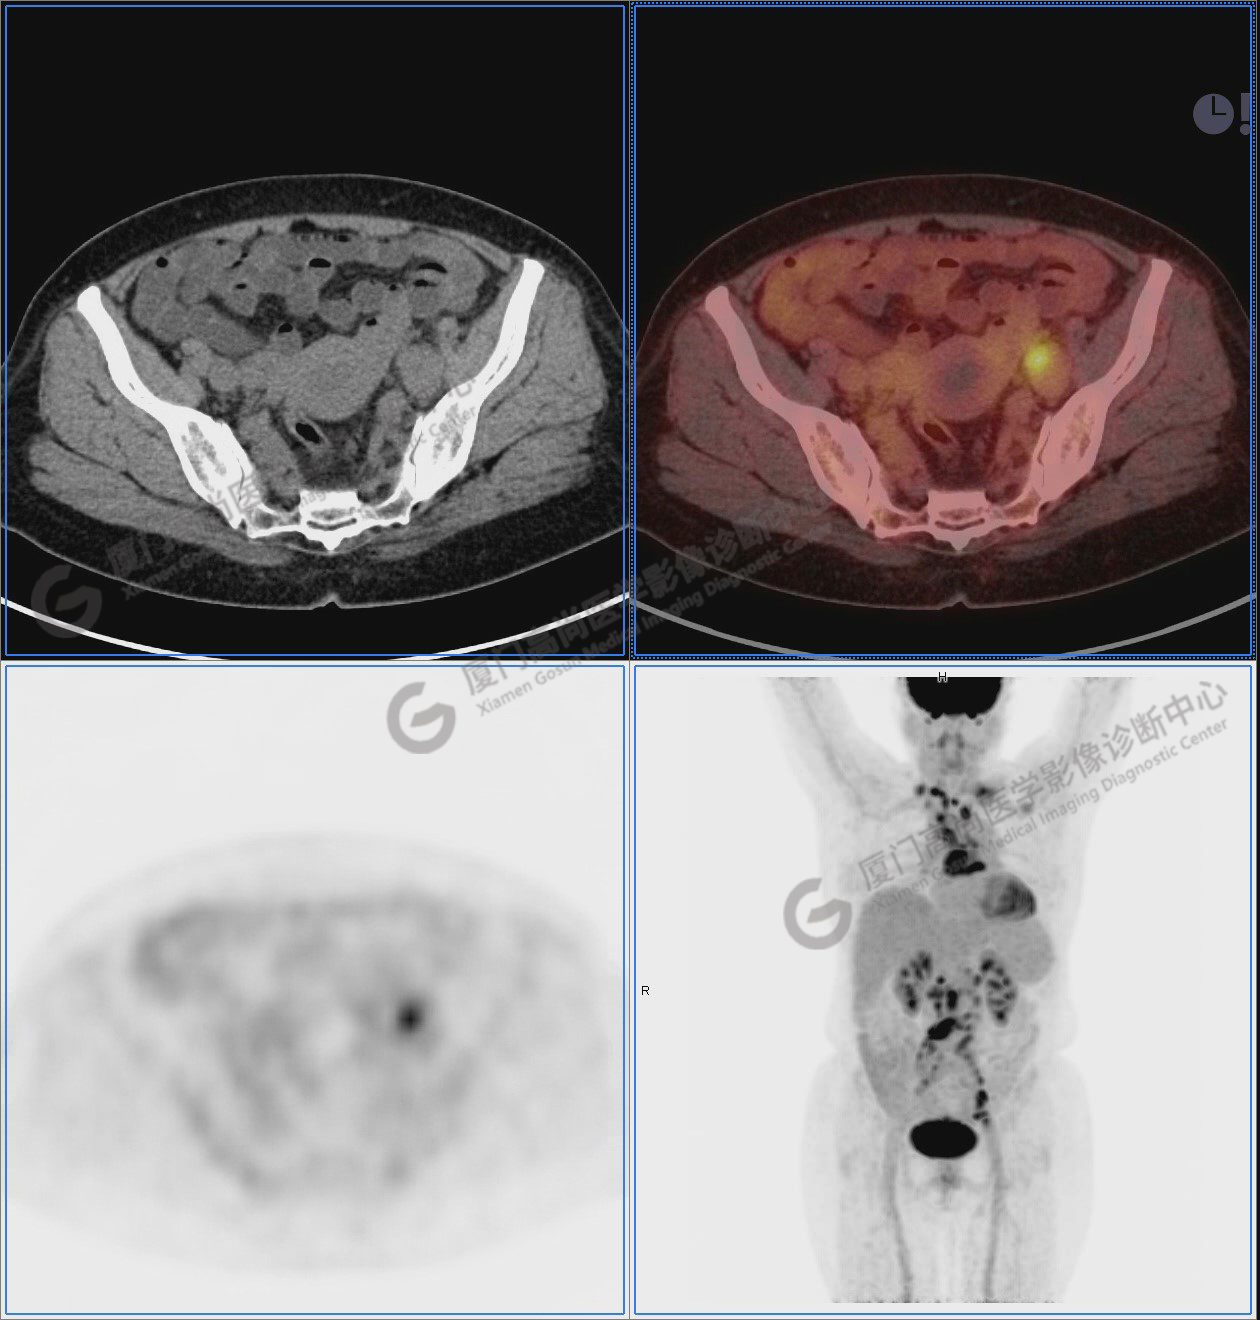

圖10-11:子宮頸軟組織腫塊,代謝異常增高,考慮為宮頸癌。

圖10

圖11